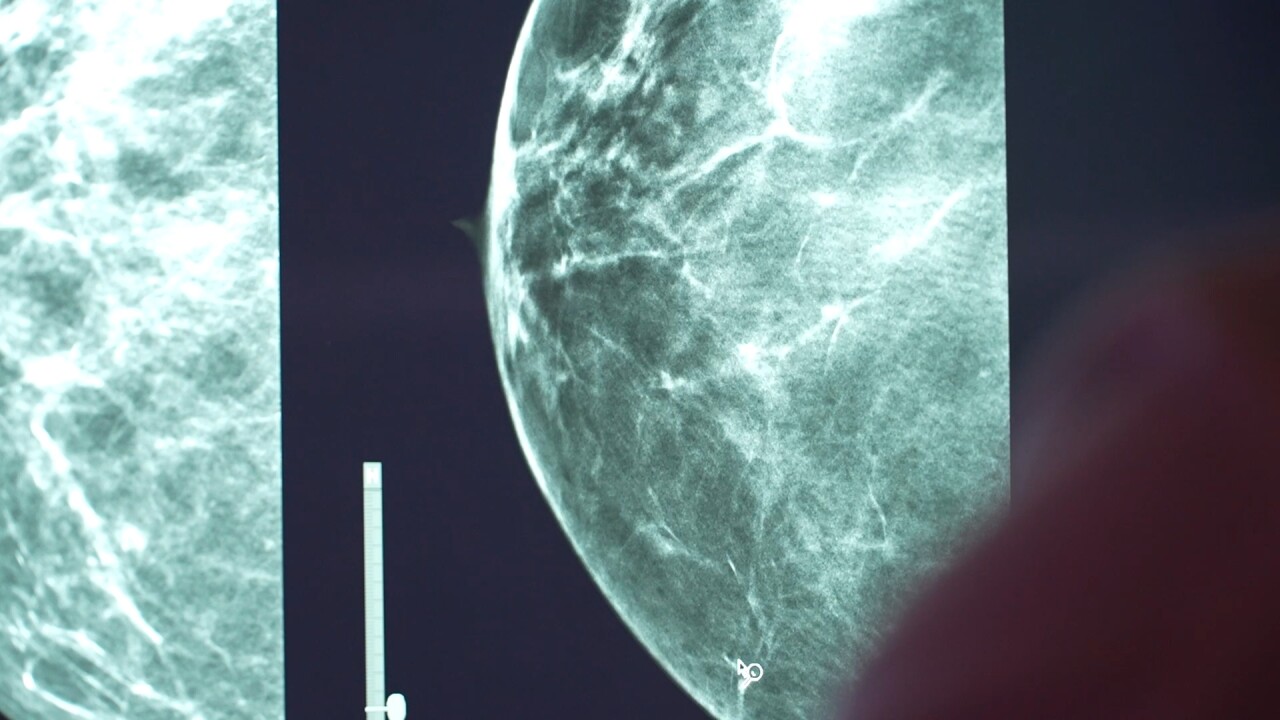

BILLINGS — For women with dense breast tissue, detecting cancer can be more difficult because tumors can be hidden or “masked” on standard mammogram scans.

Now, Billings Clinic is unveiling new technology called contrast-enhanced mammography, which uses an iodine-based dye to help doctors see what standard scans might miss.

“Basically, what it does is it subtracts a lot of the ‘busy-ness’ of the breast tissue,” he said. “Cancers and lesions can be obscured by the breast tissue. This is a tool that helps us see through that.”